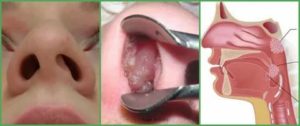

И если раньше аденоидит считался детской болезнью, сейчас выявить его у взрослых не составляет труда. Глоточные миндалины у детей расположены гораздо ниже и ближе к носу, поэтому диагностировать их не сложно.

Аденоиды в носу у взрослых расположены выше, и обнаружить их раньше не удавалось из-за нехватки оборудования.

Результативное лечение аденоидов у взрослых возможно только после полноценной, всесторонней диагностики. Для постановки верного диагноза опроса пациента и его жалоб на ночной храп, рецидивирующие синуситы и головную боль, недостаточно. Патологические нарушения в области носоглотки выявляются с помощью методик аппаратной диагностики, которая включает:

· рентгенографическое обследование – увеличенная и воспаленная миндалина просматривается на снимке, сделанном в боковой проекции;

· заднюю риноскопию – свод гортани можно рассмотреть, введя в полость рта специальное зеркало;

· компьютерную томографию – это обследование проводится с целью получения трехмерных снимков, информирующих врача о строении миндалины и структур, расположенных рядом;

· эндоскопию – состояние ротоглотки оценивается по результатам, которые выводятся на специальный монитор. Информация поступает на видеокамеру микроскопического размера, которая расположена на конце гибкого эндоскопа.

Последнее, эндоскопическое исследование является наиболее результативным, среди остальных диагностических методов. Именно благодаря эндоскопии стало возможным полноценно исследовать носоглотку, детально просматривая каждый ее миллиметр, оценивая структуры, состояние тканей и общую клиническую картину. Теперь аденоидит уже не считается чисто детским заболеванием.